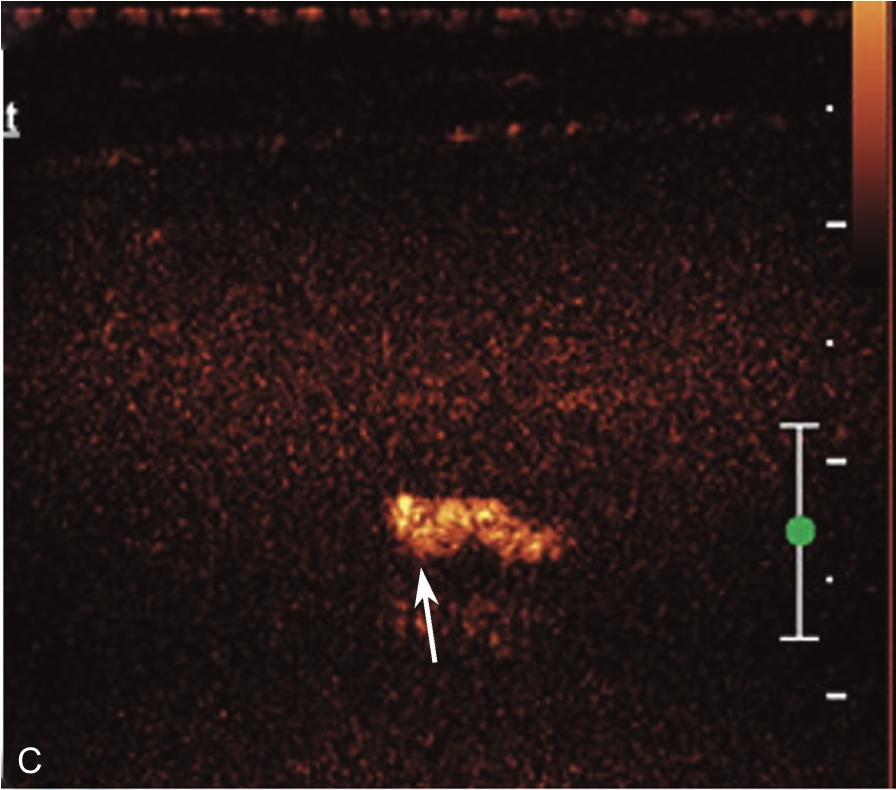

▲ 图2-1-10 超声引导下肩峰下-三角肌下滑囊造影图(三)

A.造影剂从滑囊(单箭头)及冈上肌腱撕裂处达肱骨头表面(双箭头),星号:滑囊撕裂处;B.冈上肌腱(SUP)回声不均匀,箭头:连续的滑囊,星号:滑囊回声中断,HH:肱骨头;C肱二头长头腱鞘内可见造影剂高增强(箭头);D:肱二头肌肌腱横断面(星号),腱鞘内造影剂(箭头);Del:三角肌;LT:肱骨小结节;GT:肱骨大结节